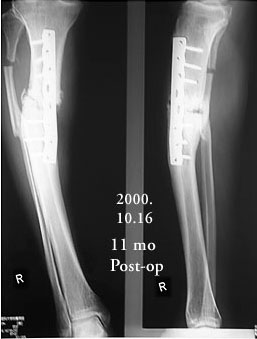

Attached are X-rays of my right leg three months after surgery with Ilizarov fixation.

According to the orthopaedic surgeon, they show solid callus formation on the medial side, while some gaps remain on the lateral side. There is no infection at the wire sites or anywhere else. The frame is to remain attached for one or two months longer. I find it to be much less of a burden than I expected. I am walking with full weight-bearing (no crutches or cane), though not yet with full balance, due to muscle atrophy. My walking is nearly pain-free, except for severe but transient pain in the center of the knee when descending stairs. I believe this is related to the unavoidably high placement of the uppermost wires, and it should cease after the frame is removed. As measured on the X-ray films, the difference in leg length is now five mm, compared with pre-op 3.5 cm. If the tibia continues to solidify and stays in its present configuration after removal of the frame, I will have escaped the judgment of Ecclesiastes 1:15 ('A crooked thing cannot be made straight'). I will inform the List of progress at six months post-op.

Attached are recent X-rays 8.5 months after surgery to correct my former 22-degree varus deformity of the right tibia. The lateral side is completely solid. There is substantial bridging of the postero-medial gap; though it is not yet complete, there appears to be no question that the surgery was successful this time. (A previous attempt using plate fixation failed.) I have been applying the SAFHS ultra-sound device to the fracture site, as directed, for 20 minutes every day for three months. All of the wire sites are clean, there is no irritation. Activities such as walking, bicycling, etc. are completely free of pain. The surgeon expects to remove the Ilizarov frame by year-end.

The case just reported by Dr Kullerkann (varus deformity of upper tibia originating from trauma 20 years previously, and similar age) seems remarkably similar to mine. While I cannot offer a medical opinion on which method would be best for that case, perhaps my case can serve as useful data. One respondent mentioned ex-fix, and as a patient I can report that this method seems to be successful in my case. The length of time required in my case is related to vascular damage from the 1971 trauma. I am looking forward to my right tibia being in better shape than it has been for 30 years.